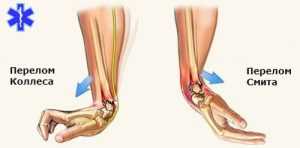

Строение запястья Если переломы костей запястья происходят по разгибательному типу, то их называют переломами Коллиса. Сгибательный перелом костей запястья называется переломом Смита. Открытые и закрытые повреждения характерны для повреждений любых конечностей. В первом случае происходит разрыв кожи и выход кости или ее фрагментов наружу.